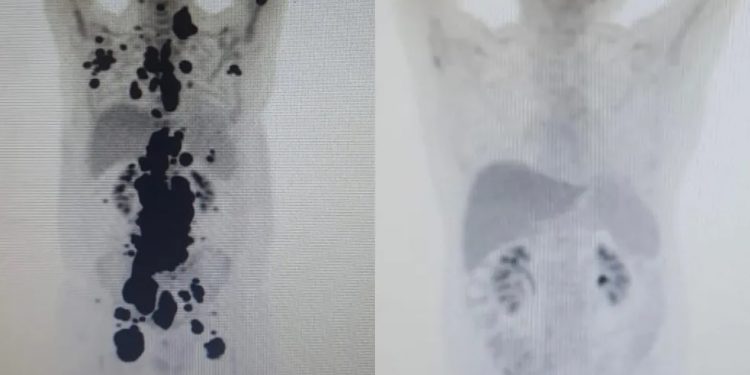

“Foi uma resposta muito rápida e com tanto tumor. Fico até emocionado [ao ver as duas ressonâncias de Paulo]. Fiquei muito surpreso de ver a resposta, porque a gente tem que esperar pelo menos um mês depois da infusão da célula. Quando a gente viu, todo mundo vibrou. Coloquei no grupo de professores titulares da USP e todo mundo impressionado de ver a resposta que ele teve”, comemorou o especialista.

As duas imagens do Pet Scan (tomografia feita com um contraste especial) (veja acima) representam “dois Paulos”: a da esquerda, o paciente que tinha como caminho único os cuidados paliativos, quando a alternativa é dar conforto, mas já sem expectativa de cura, e a da direita, um paciente com um organismo já sem tumores após o tratamento com CAR-T Cell.

“A vitória não é só minha. É da fé, da ciência e da energia positiva das pessoas. Cada uma delas ajudou a colocar um paralelepípedo nesse caminho. A imagem prova com muita clareza para qualquer pessoa a gravidade do meu linfoma, e eu não tinha ideia de que era assim”, contou o paciente.